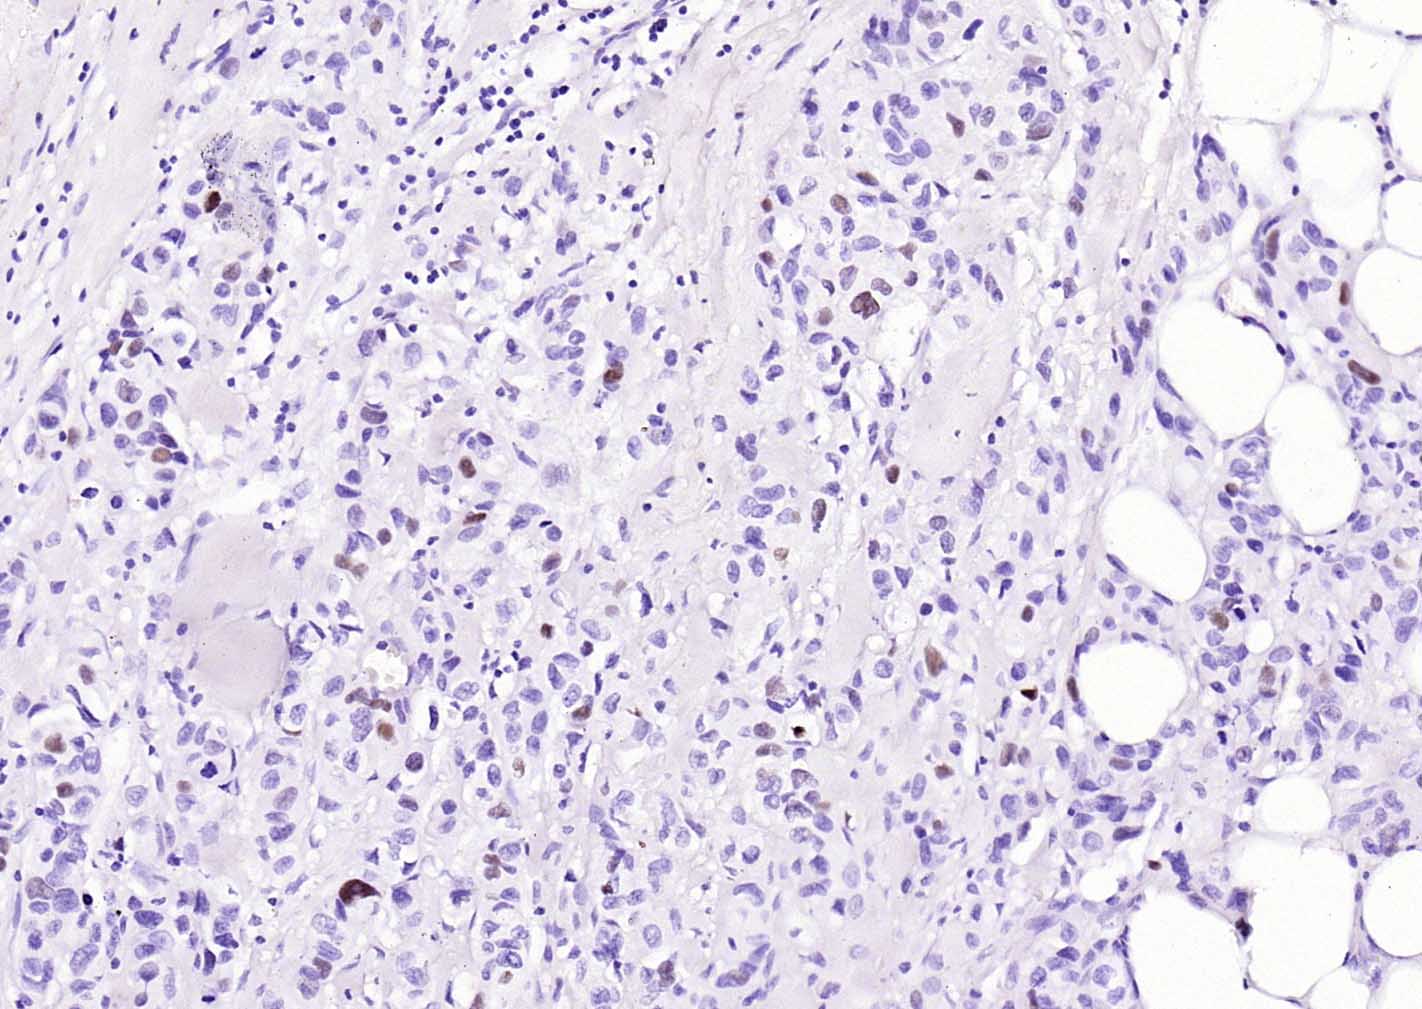

Paraformaldehyde-fixed, paraffin embedded Human Lung Cancer; Antigen retrieval by boiling in sodium citrate buffer (pH6.0) for 15 min; Antibody incubation with p53 Monoclonal Antibody, Unconjugated(bsm-60806R) at 1:200 overnight at 4°C, followed by conjugation to the bs-0295G-HRP and DAB (C-0010) staining.